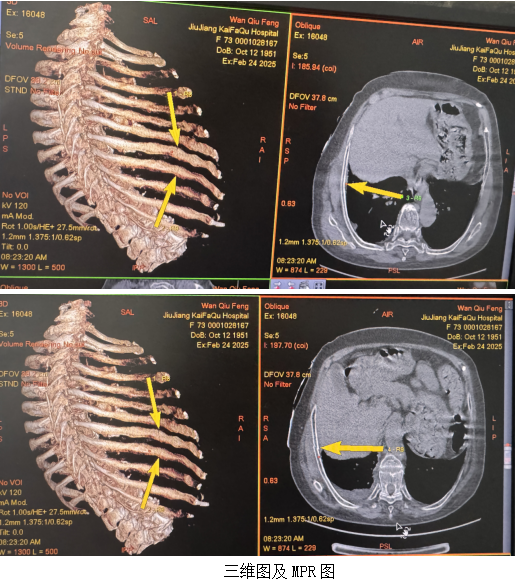

3、CT三维成像具有快速连续扫描方式和容积性数据采集的特点,并具有多角度、多平面重组的后处理功能,能任意角度地旋转观察损伤部位情况,识别细微的肋骨骨折;可将全部肋骨完整立体再现,能很好显示肋骨骨折位置、形态、数量及合并症,在对肋骨骨折诊断中具有不可替代的优势。且对法医学鉴定结果影响尤其重要。

骨折后21 ~ 40 天,骨折断端骨内膜增生成骨,可见骨痂形成,大大提高隐匿性骨折的检出率,在多平面重组图像上可见部分骨痂形成,呈现云雾状稍高密度影,边缘较模糊。

骨折41 天后,骨折断端内外骨痂增生,新生骨逐渐增多,此时在多平面重组图像上密度亦随之增高。

因此结合首次检查,21 ~ 40 天为显示隐匿性肋骨骨折复查的最佳时间段。胸部外伤所致肋骨骨折大部分涉及事故责任认定、赔偿等问题,有无肋骨骨折、骨折数量确定至关重要;复查检出肋骨骨折多为不全性或隐匿性骨折,无严重并发症,但会对司法鉴定、赔偿及量刑产生影响,建议胸部外伤后当天和4-6周后复查一次肋骨CT检查。